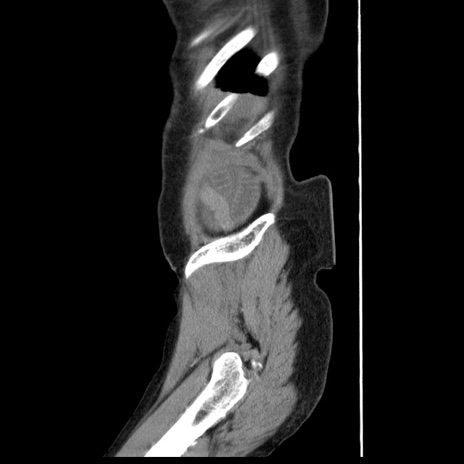

症例1(矢状断像)

【症例】80歳代女性

【主訴】腹痛

【現病歴】8時間前から腹痛あり来院。

【既往歴】糖尿病、脂質異常症、子宮体癌にて子宮全摘術

【身体所見】意識清明・会話良好だが腹痛で苦悶様、全腹部にわたって反跳痛と圧痛あり

【データ】WBC 13600、CRP 0.14、LDH 224、CK 90